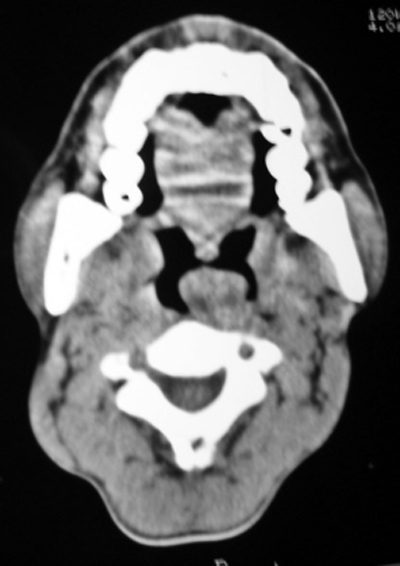

以下是引用随光逐影在2009-4-23 19:35:00的发言:[br]1)鼻咽、口咽、左侧鼻腔及右侧鼻后孔处新生物,考虑息肉可能性大。2)双侧上颌窦及双侧筛窦炎症,不排除双侧上颌窦内息肉可能。

以下是引用syfszcw在2009-4-23 13:21:00的发言:[br]双侧上颌窦 筛窦慢性炎症,鼻息肉 会厌ca[br][br][本贴已被 syfszcw 于 2009-4-23 13:36:46 修改过]

以下是引用bmw011在2009-4-23 13:23:00的发言:[br]考虑鼻息肉,上颌窦、筛窦炎